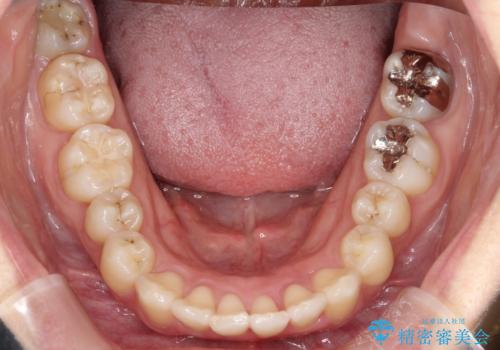

奥歯の噛み合わせは綺麗に噛んでいたため、前歯の叢生(でこぼこ)を、短期間で治療完了するように計画しました。

奥歯の噛み合わせは整っていたため、前歯の並びを美しく修正することに専念できました。マウスピース矯正による治療で短期間で改善しました。